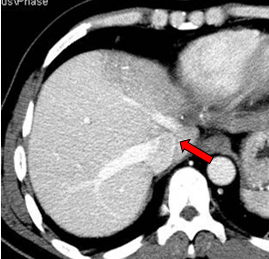

2011-01-06我院上腹部CT:

肝左叶巨块型肝癌(13.8cm×9.1cm),伴肝右后叶子灶,门静脉左支、肝左静脉及下腔静脉内癌栓。

2011-02-12复查CT示:肝左叶碘油散在沉积,病灶大部分仍有活性,肝右后叶病灶未见碘油沉积;门静脉癌栓较前进展,累及主干及右支;肝左静脉及下腔静脉内癌栓无明显变化。AFP:26802 ng/ml。